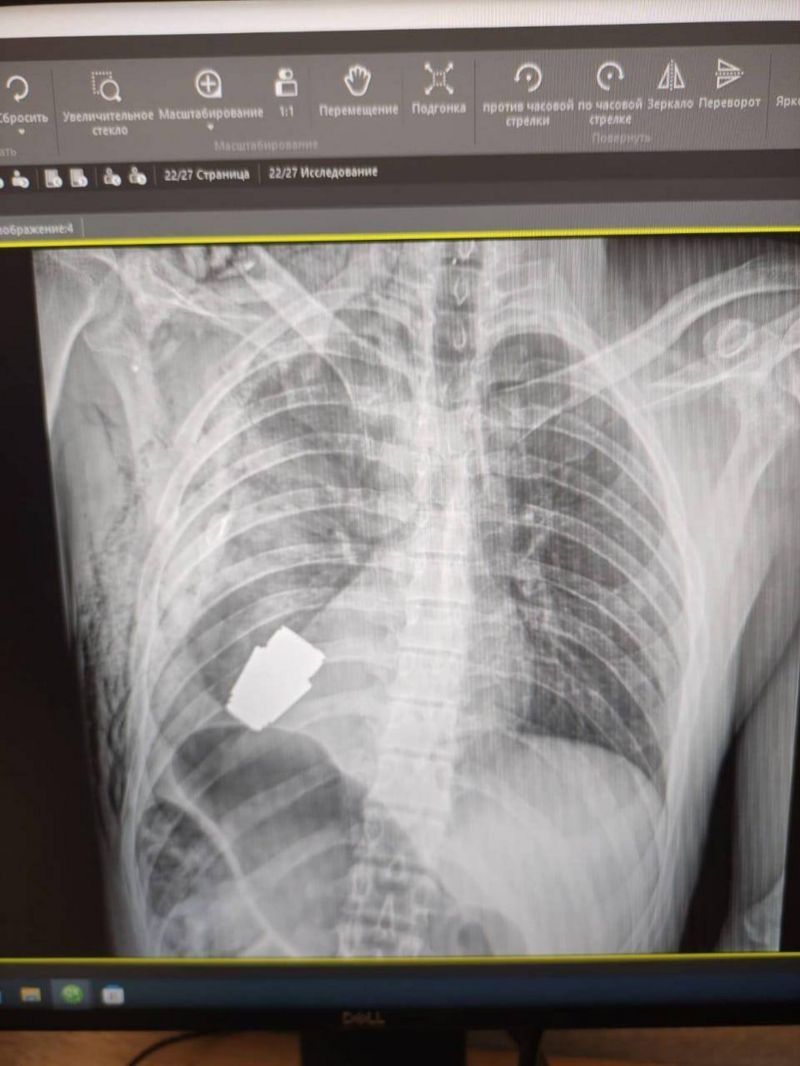

El fragmento de la granada de fabricación rusa que quedó alojado en el cuerpo del soldado tenía cuatro centímetros de diámetro y pesaba 275 gramos.